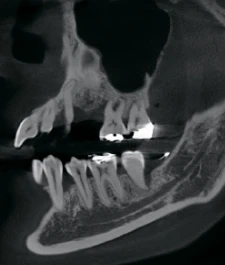

Изображения с высоким разрешением для точной диагностики

Получите исключительную чёткость изображения и настраиваемый объём сканирования с помощью RAYSCAN. Адаптируйте свои снимки в соответствии с вашими конкретными клиническими потребностями, и будьте уверены в том, что запечатлеете каждую сложную деталь и раскроете безграничные возможности.

FOV 18×16 см, 300 μm

FOV 10×10 см, 160 μm

.

FOV 4×5 см, 70 μm